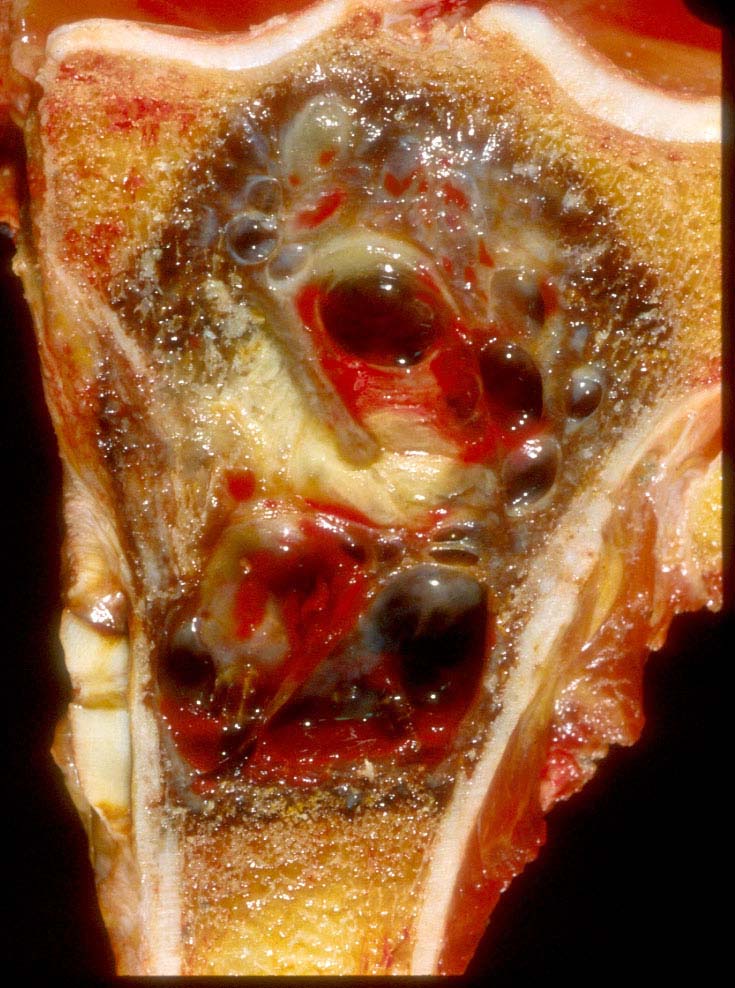

- Assessment of preoperative chemotherapy:

- Preoperative chemotherapy is commonly used with limb salvage procedures for treatment of high grade sarcomas, particularly osteosarcoma and Ewing sarcoma

- It is generally required to quantify the extent of tumor necrosis as a percentage of the total tumor area

- For osteosarcomas, chemotherapy induced necrosis of ≥ 90% has a > 90% disease free survival, compared with < 50% in patients with < 90% tumor necrosis

- To determine the extent of necrosis in an osteosarcoma or Ewing sarcoma specimen, the slab specimen of the resected bone containing tumor provides the template for histologic analysis

- Photograph of the slice is taken and the site of each numbered block is marked on a grid pattern diagram

- Status postneoadjuvant chemotherapy:

- To gross: cut along long axis of tumor and map

- Status postneoadjuvant chemotherapy:

- Report treatment response as a percent tumor necrosis (really an assessment of tumor drop out)

- Edematous scar: loose edematous to myxoid granulation tissue, fibrosis, mild chronic inflammation

- Bony matrix remains

- Residual tumor cells: nests of tumor cells in retraction clefts are common

- Grading response to chemotherapy (same cutoffs as Ewing sarcoma) (Cancer 1993;72:3227, J Clin Oncol 1988;6:329):

- Good response is > 90% tumor necrosis

- Report treatment response as a percent tumor necrosis (really an assessment of tumor drop out)